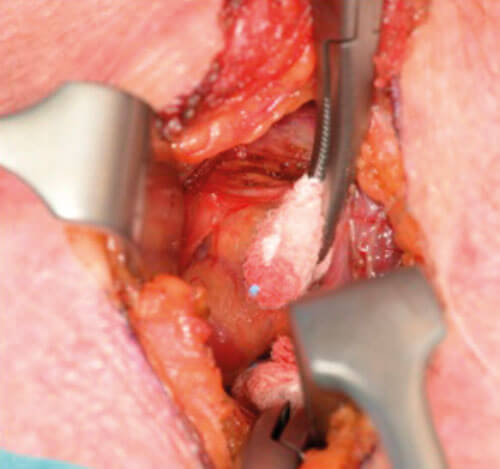

Figure 10. Identification of the PT gland in the exact predicted location.

There are several advantages to using this technique. The primary advantage of this method of targeted location is the reduced risk to surrounding structures as the dissection area is minimised. Therefore, there is a reduced risk of damage to the recurrent laryngeal nerve and to healthy PT glands. Targeted location makes the procedure more efficient and reduces the risk of failure of operation as it will be unlikely to remove the wrong gland given the correct measurements from the scan.